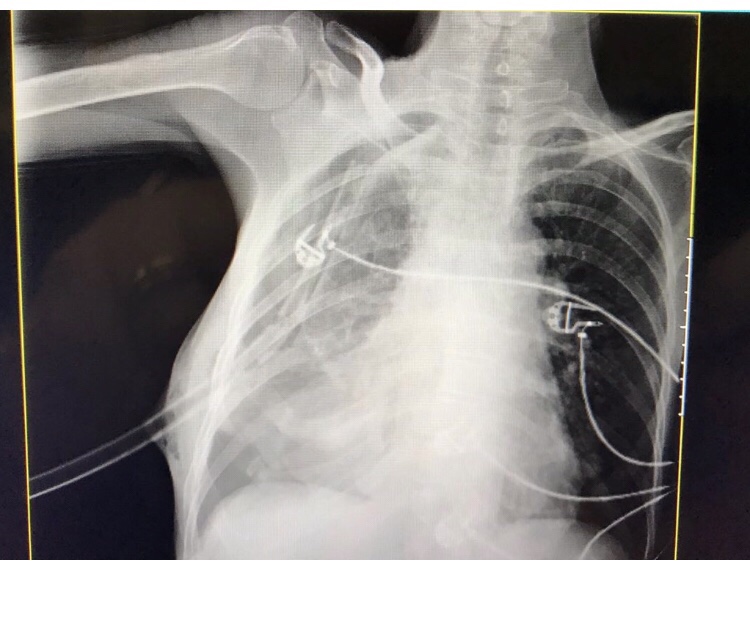

Mas como houve melhora da dispnéia, e a possibilidade de realização do exame, foi optado por TC de toráx com contraste para melhor avaliação do quadro pulmonar, por se tratar de história arrastada e grande possibilidade de coleções, antes de realizar o dreno de toráx.

Laudo:

Esofago acentuadamente dilatado, exibindo provável soluções de continuidade adjacentes em sua parede medial ifnerior direita com a cavidade pleural de aprox 0,9cmx1,4cm, notando-se acentuado derrame pleural com material heterogêno com focos gasosos, devendo representar conteúdo alimentar. (sem demais alterações)

Quadro clínico e achados compatível com Perfuração de Esôfago!

Realizado drenagem de toráx de conteúdo turvo e alimentar.